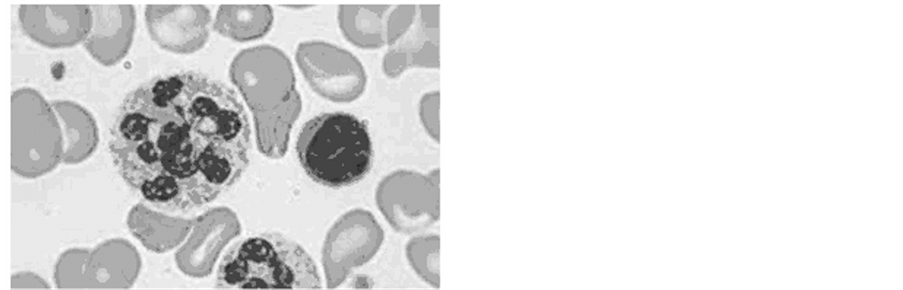

In order to identify the possibility of using wavelet analysis as a processing tool for cytology preparations images for various color models, some image have been selected. The test image is shown in Figure 1 (image cells in pernicious anemia). This image is analyzed in our other articles and gives an opportunity to make a comparative analysis [8] .

This image reflects common features in the analysis of cytological drugs. We can see the different types of cells, the complex structure of the cell. This image allows us to test the possibilities of wavelet analysis, which we described earlier [8] [10] [11] .

In Figure 1, we see one of the varieties of pernicious anemia-this is megaloblastic anemia. Megaloblastic anemia is a blood disorder marked by the appearance of a very large red cells (cells of blue color) that crowd out of a healthy cells (cells of red-pink color), causing anemia.

Figure 1. Image cells in pernicious anemia.